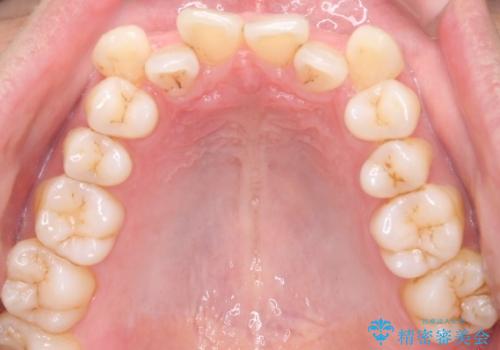

- 治療計画

叢生量が大きいため、上下顎両側4番を抜歯しました。矯正治療による歯肉退縮の著しい悪化もなく、主訴であるガタつきも改善できました。